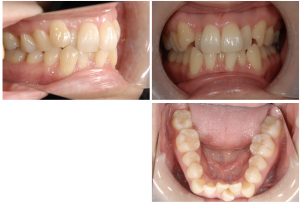

インビザラインによる抜歯症例

初診、叢生が強度で正中線が下が左側にずれています。奥歯は左右1級ですが、抜歯の診断になりました。インビザラインを希望。

上は左右4、右下5、左下4を抜歯してインビザラインをスタート、ボタンも装着して顎間ゴムを併用します。

追加のアライナー(マウスピース)も5回程度行い、顎間ゴムもしっかり行い、なんとか前後的には1級をキープして抜歯スペースを閉じましたが、特に下顎の奥歯が近心傾斜を起こし、上下の臼歯の咬合にスペースができてしまい噛んでいないため、ここから下顎のみ表側のマルチブラケット矯正装置に移行しました。インビザラインでは奥歯の傾斜と前歯の早期接触で上下の奥歯の噛み合わせに隙間ができることが結構多いです。